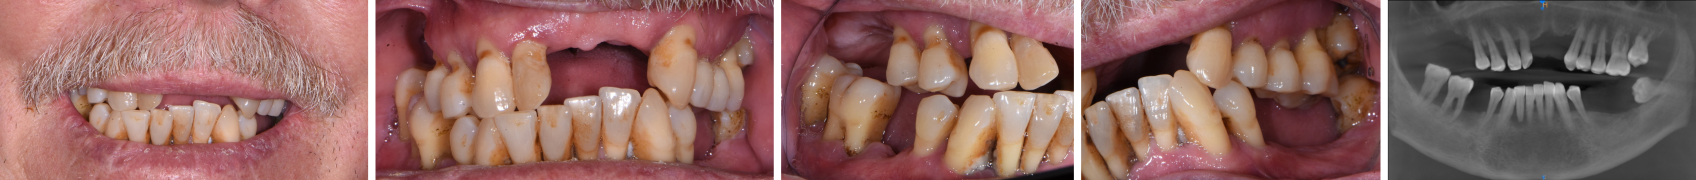

As a comparison, let me walk you through a case I did not long ago, using a CEREC Primescan digital scanner. The patient (Figs. 1–5) was referred by a retired dentist who had worked with one of my primary periodontists, with whom I treated this case.

After reviewing treatment options with the patient, we decided to start with immediate upper and lower dentures, with the understanding we could reconsider implants as needed or desired. We discussed that, at a minimum, we’d eventually need to reline the dentures, and even with relines, we might need to fabricate a new set of dentures after his hard and soft tissues had healed and the initial ridge resorbed.

After evaluating the case further, my periodontist and I decided he would extract some posterior teeth before I scanned the patient and had the immediate dentures printed. Figs. 6–8 show the patient after those extractions; Figs. 9–14 are the scans I took.